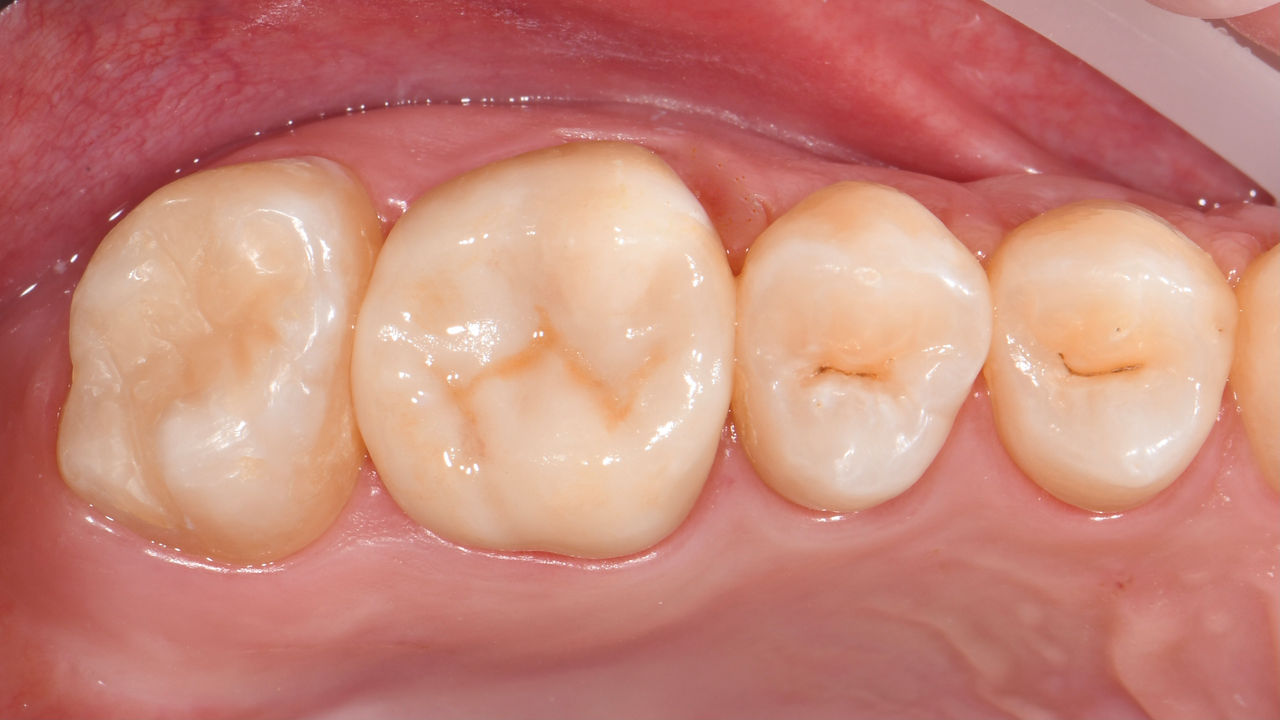

Before: Insufficient fillings in the second quadrant. The restorations were about 15 years old.

After: Chairside-fabricated crowns made from CEREC Tessera (teeth 26/27). Inlays for teeth 24 and 25 made of composite blocks.